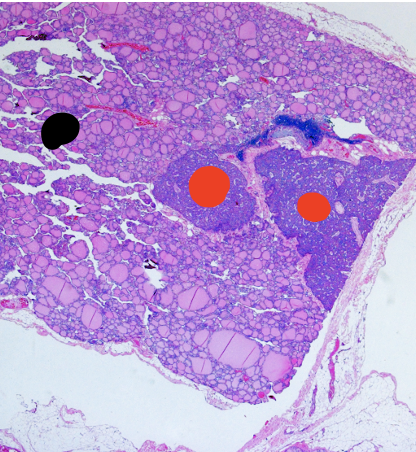

Thyroid gland

black arrow –> capsule

Follicles

Black –> thyroid

Red –> parathyroid